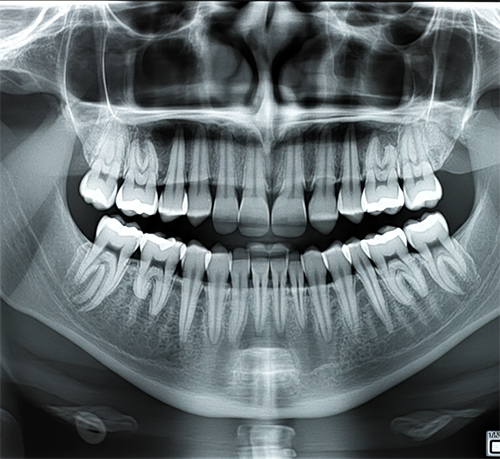

This dental X-ray shows normal tooth structures with good bone support. All dental anatomy appears within normal limits.

CT Read's Dental X-ray Interpretation is an AI-powered tool that helps non-medical users understand their dental X-rays. Using advanced image analysis, the technology identifies teeth, roots, bone structures, and potential issues in dental radiographs, explaining findings in simple, everyday language anyone can understand.

Understanding dental X-rays is valuable for anyone wanting more insight into their oral health. The AI analysis helps identify common findings like cavities, bone loss, impacted teeth, and root issues - giving you clearer understanding before dental appointments and helping you have more informed conversations with your dentist.